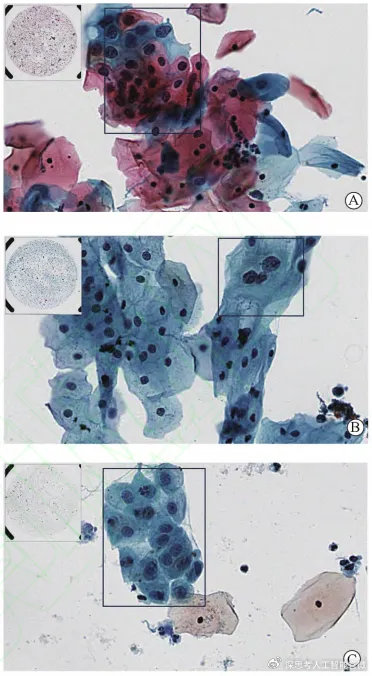

Cervical cancer is one of the common malignant tumors in gynecology. thinprep cytologictest (TCT) is an important means of cervical cancer screening. At present, the lack of cervical cytology readers and diagnostic experience makes it difficult to meet the needs of cervical cancer screening. In this case, the diagnosis efficiency and accuracy of pathologists can be improved by using AI multimodal model to assist doctors to analyze the multimodal information of patients.

In order to verify the auxiliary effect of AI, the Pathology Department of Henan Provincial People’s Hospital selected a total of 86,000 liquid-based thin-layer cervical cytology smears from January 2019 to December 2020, and analyzed the samples with artificial intelligence cytology-assisted reading system, and compared the analysis results with the original diagnosis results.The grading diagnosis result of the artificial intelligence cytology assisted reading system is close to the biopsy result.Table 1; Out of 6880 samples with positive original diagnosis results, 2500 HPV positive samples were selected for grading diagnosis experiment, and the grading results of reading films by artificial intelligence cytology auxiliary screening system were basically the same as those of HPV positive detection results (Table 2). The analysis results show that the sensitivity and specificity of the artificial intelligence cytology-assisted reading system can reach 98.77% and 74.16%.With the help of artificial intelligence cytology-assisted reading system, the sensitivity and specificity of pathologists are improved, with sensitivity of 100% and specificity of 99.99%.

Beijing Chaoyang Hospital, affiliated to Capital Medical University, also selected 1,000 TCT smears with definite diagnosis from January 2019 to August 2019. Professional pathologists make cytological diagnosis by reading under microscope, and the artificial intelligence cervical cancer auxiliary screening system adopts digital cervical smear and intelligent reading. The results showed that the screening results of pathologists and artificial intelligence were close to the standard samples.With the aid of artificial intelligence, the diagnostic accuracy of pathologists for 1,000 samples can reach 99.80%, and the sensitivity is as high as 100%.

Compared with the traditional diagnosis method that only depends on the pathologist’s reading under the microscope, comprehensive analysis of cytology, medical history, medical records, age and other multimodal information by using AI medical multimodal model can greatly help pathologists improve the diagnostic level and efficiency, effectively reduce the interference of unfavorable factors such as artificial skill level and fatigue, and handle more cervical cytology slides while reducing the possibility of leakage and misdiagnosis.